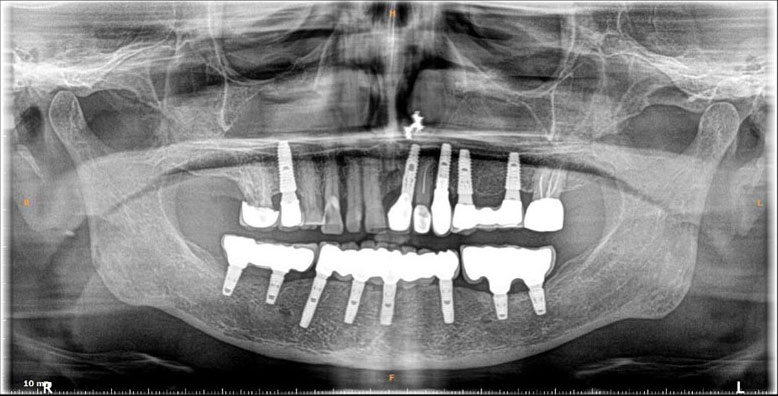

Dental implants are artificial tooth roots use to replace decayed or missing teeth. They are a popular and effective long-term solution, dental implants are placed into the jawbone, providing a stability for replacement teeth.

They serve great benefits like enhancing one's smile and facial structure, provide stability and support allowing to eat and speak freely.